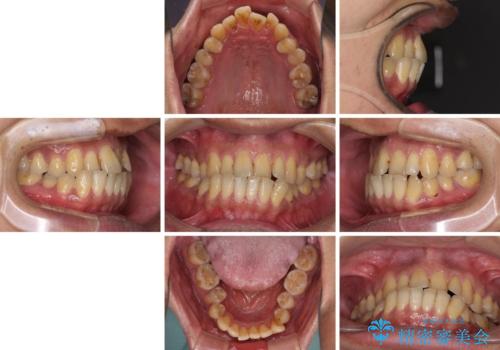

前歯のクロスバイトを改善 ワイヤー装置での非抜歯矯正

- 骨格的な咬み合わせのズレ、前歯のデコボコとクロスバイトを気にして来院された患者様です。

骨格のズレが顕著であると診断され、マウスピース矯正では奥歯の咬み合わせが整えにくいと判断し、ワイヤー装置による矯正治療を行うこととしました。

上下の叢生は速やかに改善できましたが、右側のクロスバイトの改善に1年以上の期間を要しました。